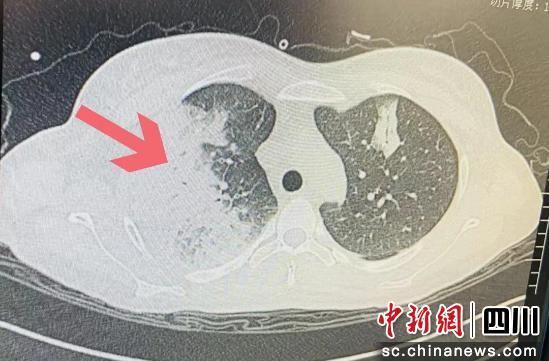

作為一名剛懷孕7周的孕婦,此時小梅已經(jīng)出現(xiàn)不明原因反復(fù)發(fā)燒4天,最高燒到40℃,還伴有寒戰(zhàn)、咳嗽、白痰、眩暈等癥狀,拍片還發(fā)現(xiàn)她的肺部感染嚴(yán)重,已經(jīng)出現(xiàn)了大面積的“白肺”。

入院后,小梅已出現(xiàn)嚴(yán)重低氧血癥,胸部CT顯示雙肺大面積"白肺"伴胸腔積液,情況已經(jīng)十分危急。